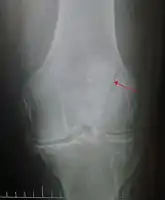

Vertical patella fracture

Differential diagnosis

Some people have a normal two-part patella which can appear as a fracture. The fragment is usually seen in the top outer corner of the patella and can be distinguished from a fracture by being present in both knees.[6]